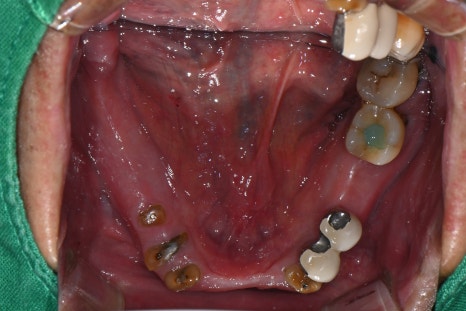

하악 보험 임플란트 식립 후 의 모습

한달 후 상악 전체 발치 진행한 모습